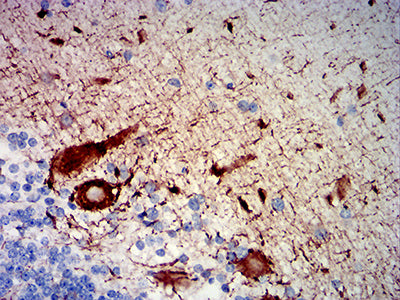

-